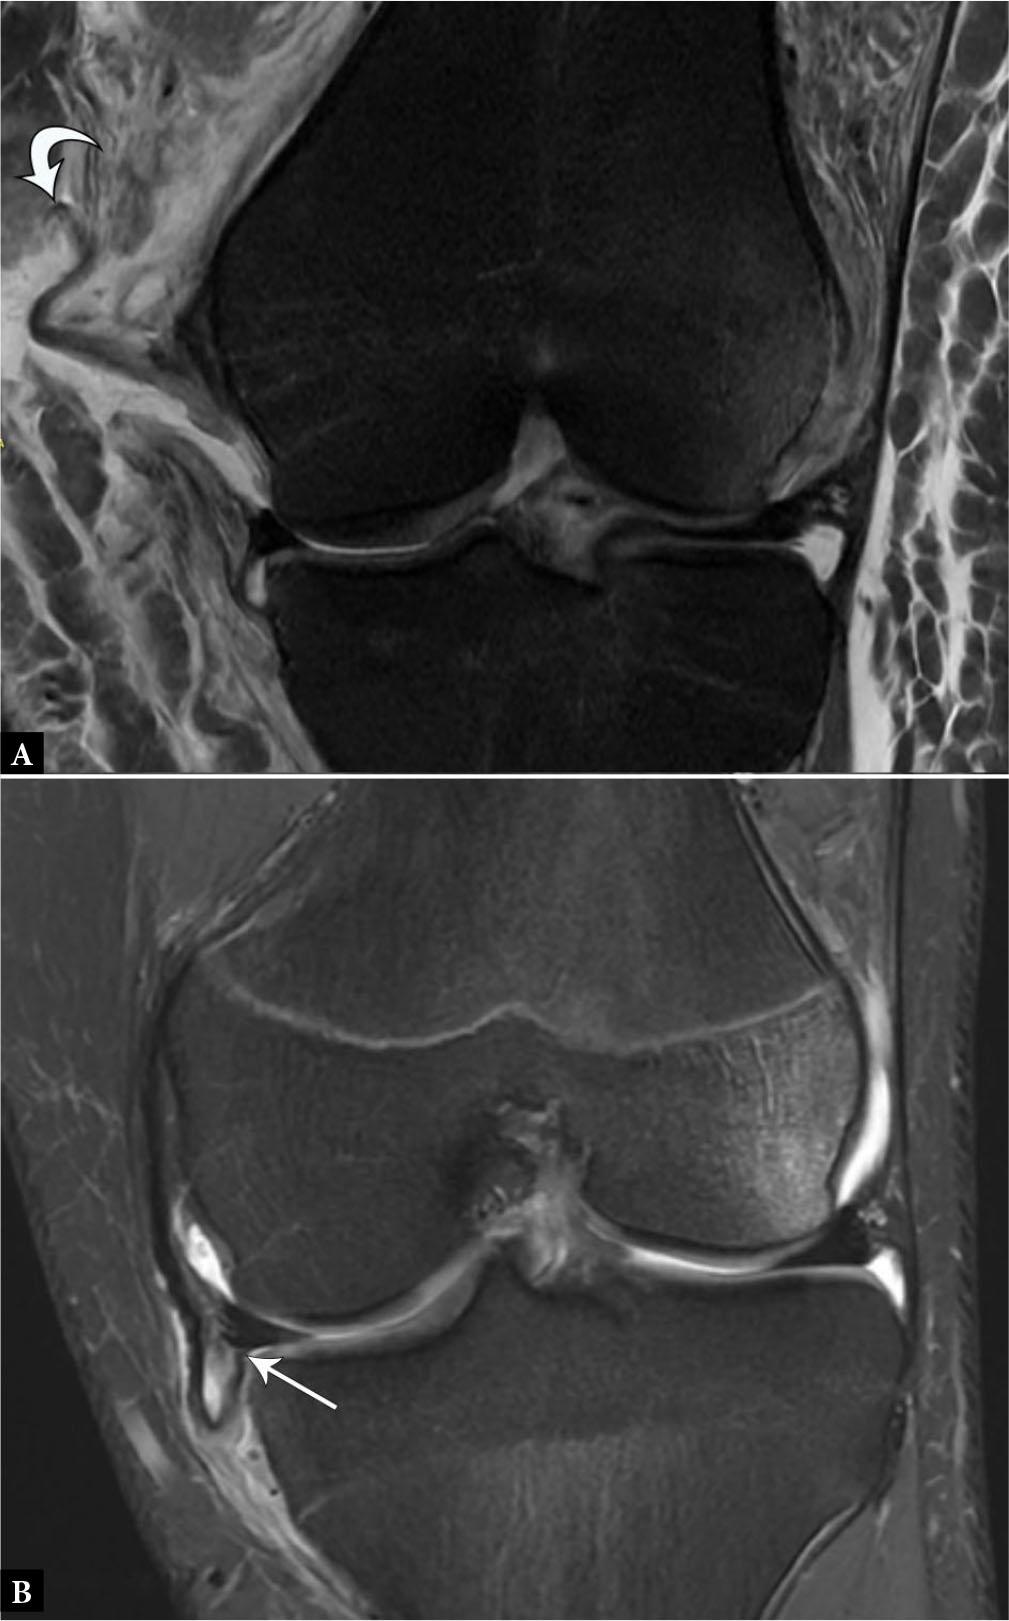

Fig. 11.

A. 19-year-old male with displaced MCL tear. Coronal proton-density-weighted fat-suppressed MR image shows completely torn and proximally displaced MCL stump (curved arrow) superficial to the pes anserinus, consistent with a Stener-like lesion. B. 16-year-old male with flipped and entrapped MCL tear. Coronal proton-density-weighted fat-suppressed MR image shows completely torn and proximally displaced MCL stump entrapped at the medial joint line inferior to the meniscus (arrow), which also requires surgical repair despite lying deep to the pes anserinus.